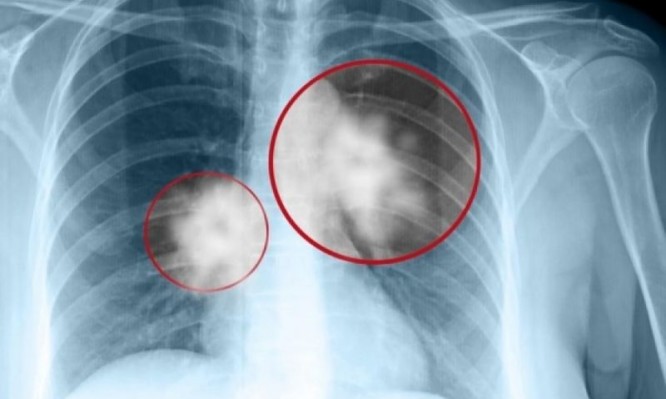

Κατά τα άλλα, τι περιμένατε; Το ακούσαμε από τα πλέον έγκυρα χείλη ότι το 85% των ασθενών με καρκίνο του πνεύμονα ήταν ή είναι καπνιστές. Και κάποιοι από τους υπόλοιπους που ανήκουν στο 15%, ήταν επί σειρά ετών παθητικοί καπνιστές. Για τους υπόλοιπους, αναζητούνται «ένοχα» γονίδια που «προς το παρόν», όπως επισήμανε ο κ. Συρίγος, δεν μπορούμε να αλλάξουμε…

Πάντως, το προσδόκιμο επιβίωσης όσων πετυχαίνουν διάγνωση σε πρώιμα στάδια καρκίνου του πνεύμονα, κάνουν χειρουργική επέμβαση και θεραπεία και συνεχίζουν την ζωή τους κανονικά… Και στους υπόλοιπους, με πιο προχωρημένα και επιθετικά είδη καρκίνου του πνεύμονα, υπάρχουν πολλά να γίνουν και ζουν πια αρκετά χρόνια… Γενικά έχει περάσει πια η εποχή που ο συγκεκριμένος καρκίνος οδηγούσε αμέσως στο θάνατο.

Παρόλα αυτά, όπως μας είπε ο καθηγητής, είναι σημαντικό τα άτομα της ομάδας υψηλού κινδύνου (καπνιστές) να οδηγούνται αμέσως στο πνευμονολόγο αν χειροτερέψει ο βήχας τους, έχουν δύσπνοια, ή έχουν πτύελα με αίμα ή νιώσουν πόσο στη μέση και το στήθος… Όσο πιο γρήγορα γίνει η διάγνωσή τους, τόσο πιο σίγουρο είναι ότι θα ιαθούν.